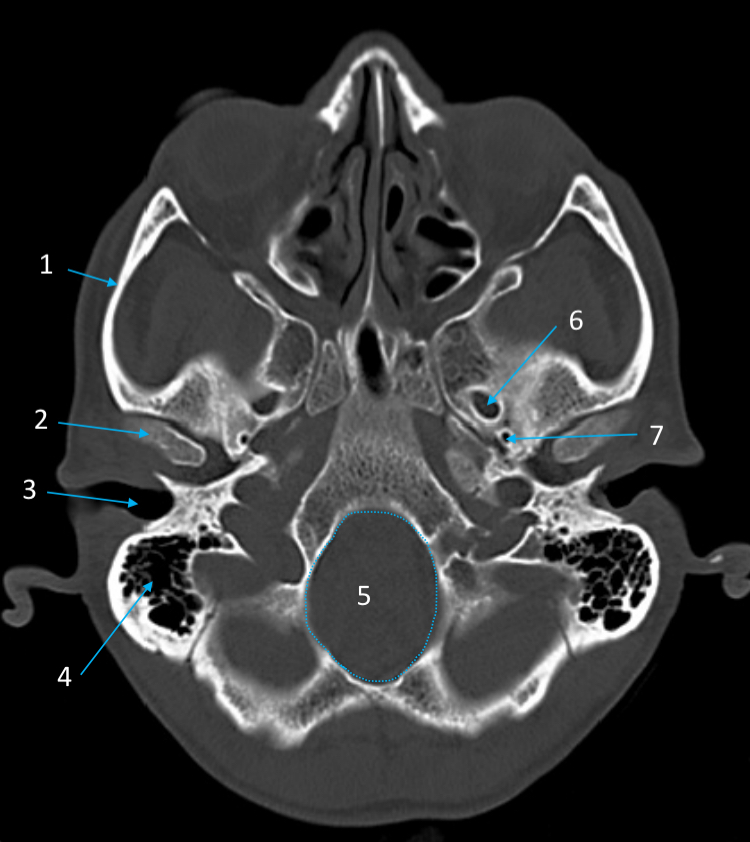

Mandible

ID bone

Maxilla

ID bone

Frontal sinus

ID structure

Pituitary fossa

ID structure

Occipital

ID bone

Lambdoid suture

ID structure

Frontal sinus

ID structure

Orbital margin

Orbit

Maxillary sinus

ID structure

Mandibular condyle

ID structure

Inferior nasal concha

ID structure

Hard palate

ID strucutre

Gonial angle

ID strucutre

Petrous ridge

ID structure

Groove of middle meningeal a.

ID structure

Roof of orbit

ID structure

Frontal sinus

ID structure

Pituitary fossa

ID structure

Petrous ridge

ID structure

Sphenoid sinus

ID structure

Hard palate

ID structure

Mastoid air cells

ID structure

Zygomatic arch

ID structure

Mandibular condyle

ID structure

External auditory meatus

ID structure

Mastoid air cells

ID structure

Foramen magnum

ID structure

Foramen ovale

ID structure

Foramen spinosum

ID structure